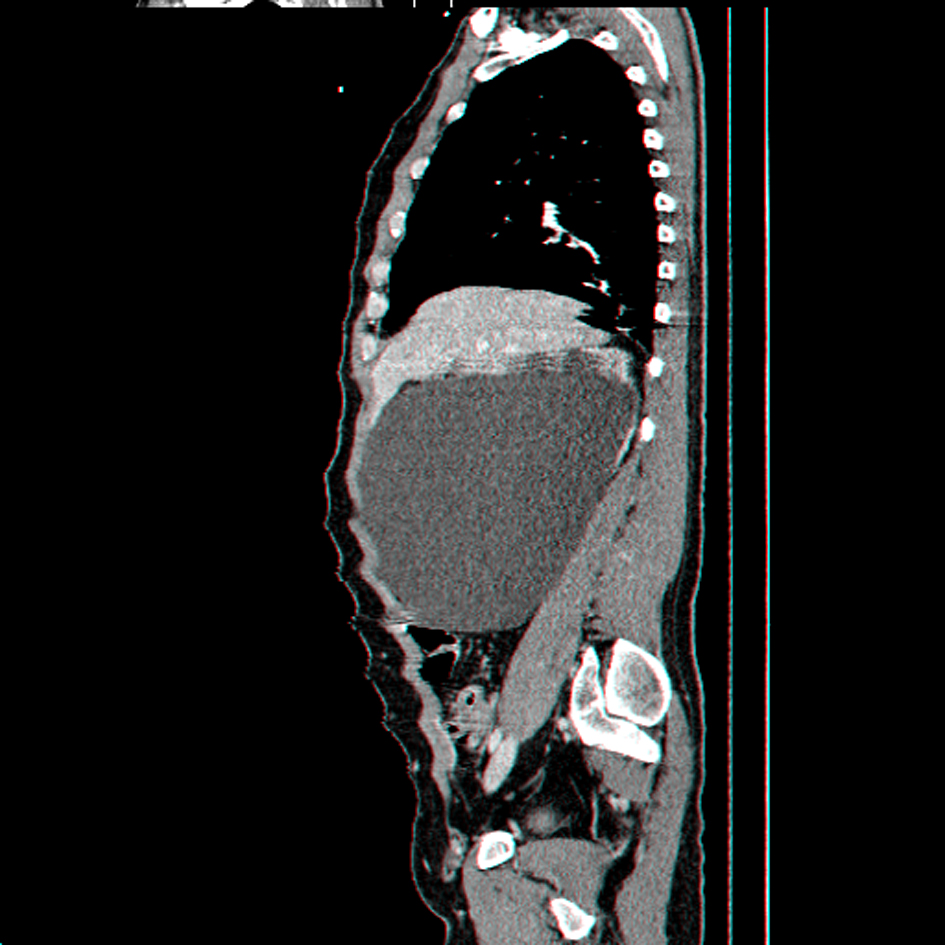

A 27-year-old man, dumb, deaf and with mild mental retardation, presents in the Emergency Room (ER) with sepsis secondary to community-acquired pneumonia. During assessment in the ER was detected a large painless abdominal mass, localized in the right upper quadrant and extending into the pelvis. He had no prior history of colic, urolithiasis, or infection. Computed tomography revealed severe right hydronephrosis and thinning of renal parenchyma (Fig. 1, 2) due to probable congenital UPJ obstruction, with compression of adjacent viscera and lateralization of the great vessels (Fig. 3). The left kidney was normal. Blood analysis presented a normal renal function.

![]() Click for large image | Figure 2. Sagital reconstruction CT scan showing giant right hydronephrosis occupying most of the abdominal cavity. |